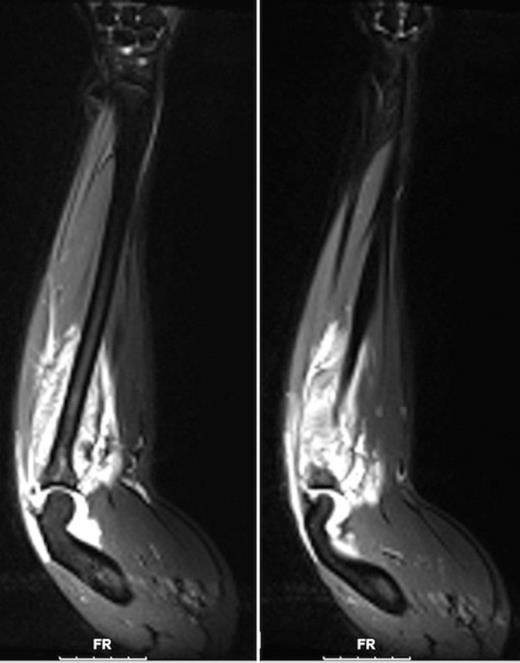

A 15-year-old male with nephrotic syndrome diagnosed at 1 year of age presented with acute onset of right forearm swelling and pain over 2 days, worsening acutely over 8 hours prior to consultation by the plastic surgery service. He denied any precipitating trauma or inciting event. On examination he was found to have tense swelling over the proximal dorsal aspect of his forearm, with severe pain on passive flexion of his wrist and fingers. Radial and ulnar pulses were palpable, and sensation was intact to all fingers. Compartment pressures were measured, and showed elevated pressures in the dorsal forearm compartment of 70 mmHg, with a volar forearm compartment pressure of 14 mmHg. MRI had previously been ordered by the pediatric medicine service, and showed muscle edema concerning for myositis in the dorsal compartment of the forearm (Fig. 1). Due to swelling localized to the dorsal forearm as well as elevated pressures in the dorsal forearm compartment only, the presumptive diagnosis was compartment syndrome localized to the dorsal forearm compartment.

MRI of the forearm (coronal sections) shows enhancement on T2-weighted images suggesting edema in the region of the ulna (left) and dorsal forearm musculature (right).